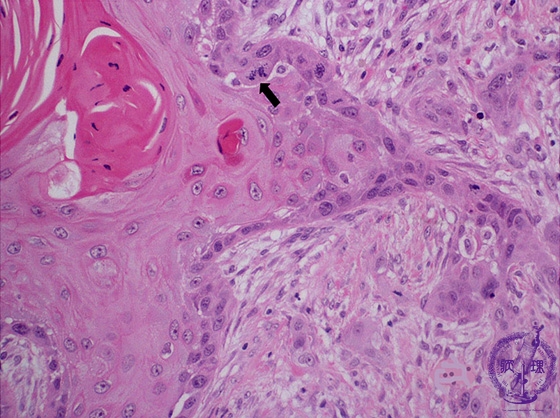

- ★(6)Oral cancer (Squamous cell carcinoma)

Microscopic finding (HE stain, high-power view):Despite exhibiting keratinization and recognizable stratified squamous cell epithelium architecture, there are characteristic features of cancer such as nuclear pleomorphism and atypical mitoses (arrow).